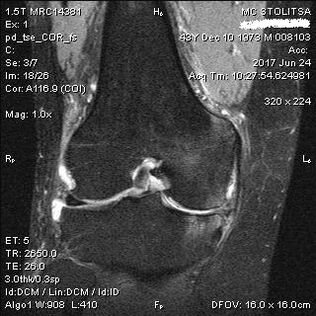

La diagnosi di artrosi dell'articolazione del ginocchio avviene nello studio di un reumatologo o di un ortopedico. Il medico esamina l'articolazione interessata, la palpa, ascolta i reclami e pone ulteriori domande. Esegue diversi test, ad esempio chiedendo al paziente di piegare la gamba o fare qualche passo. Quindi, se è necessario chiarire lo stadio della malattia o la natura dei cambiamenti patologici, ti indirizzerà per ulteriori studi. Ad esempio, per la tomografia computerizzata o la radiografia.